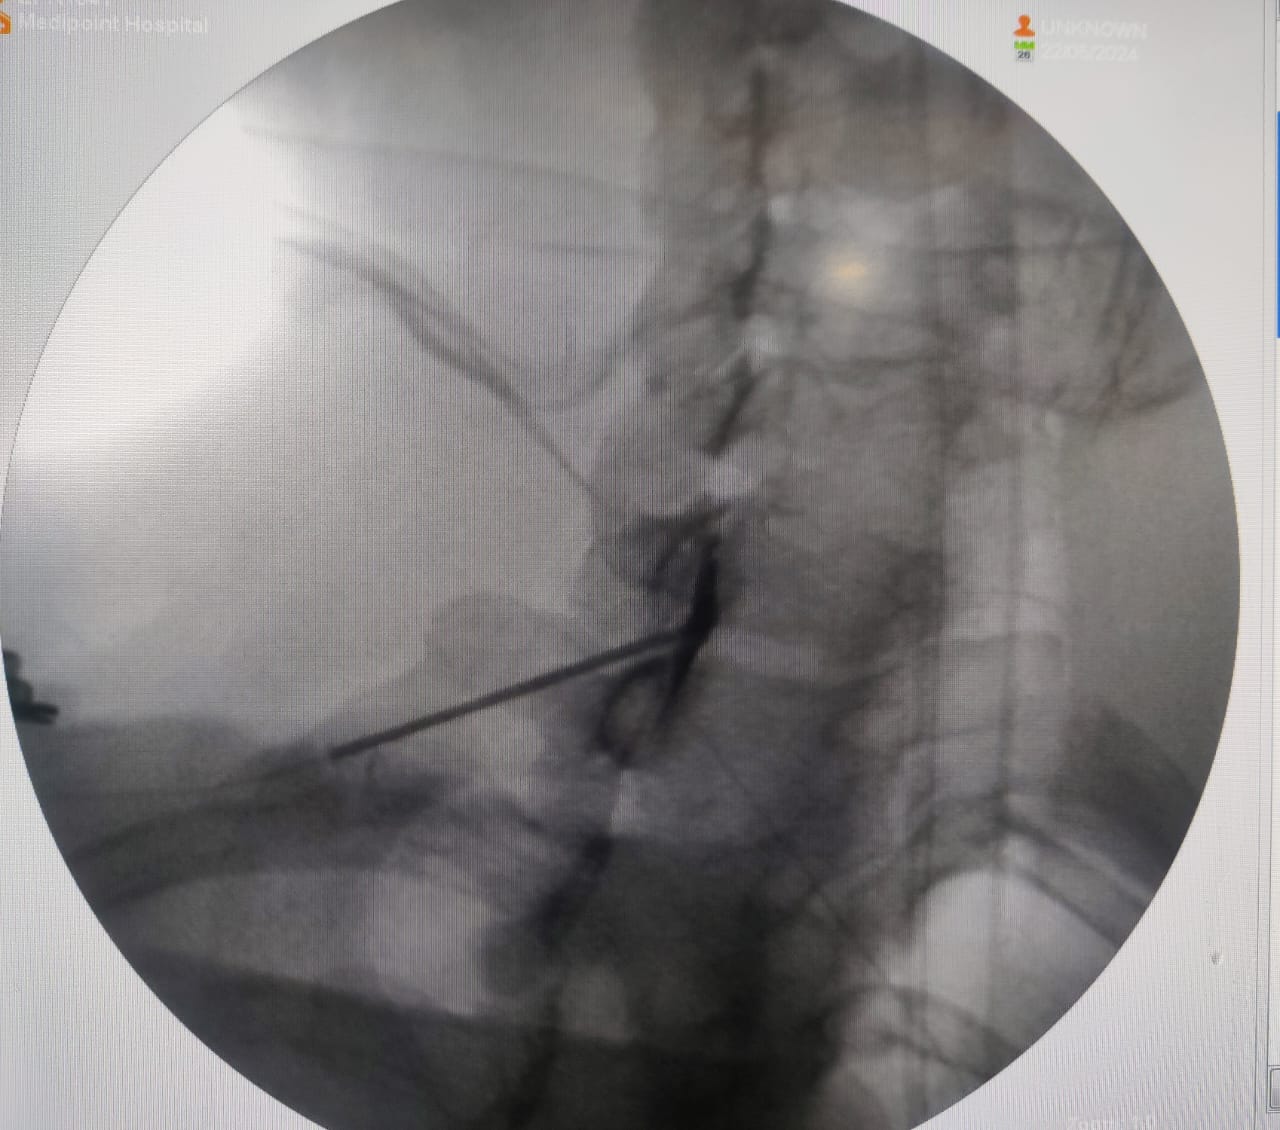

- Fluoroscopy (live X-ray) is used to guide the needle to the correct location in the epidural space, which is the area surrounding the spinal cord and nerve roots.

3. Injection:

- A mixture of corticosteroid (to reduce inflammation) and a local anaesthetic (for immediate pain relief) is injected into the epidural space.